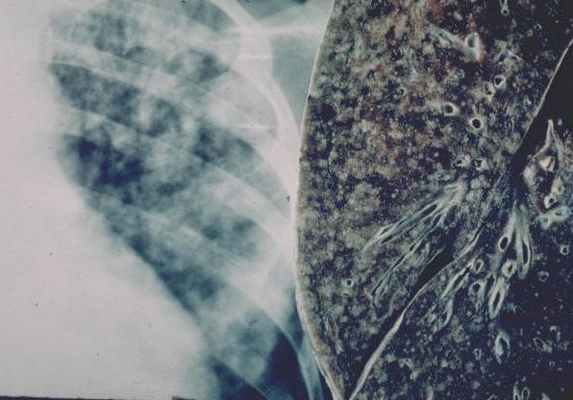

12. Диссеминированный туберкулез легких характеризуется двусторонней очаговой диссеминацией, преимущественно с субплевральным

расположением очагов,

распространением их сверху вниз и наличием

внелегочных очагов поражения

23. Острый диссеминированный туберкулез характеризуется двусторонней симметричной мелкоочаговой мономорфной диссеминацией,

распространяющейся сверху вниз, с

субплевральной локализацией и наличием

внелегочных очагов поражения.

28. Рентгенологическая картина острого диссеминированного туберкулеза

• На рентгенограмме на 7 – 8 день от начала

заболевания отмечается снижение прозрачности

легочных полей по типу «матового стекла»

• На 10 – 14 день появляются мелкие мономорфные

очаговые тени в обоих легких, симметричные,

преимущественно в верхних и средних легочных

полях

Туберкулиновые пробы обычно ложноотрицательные. При рентгенологическом исследовании выявляются множественные, хорошо отграниченные и расположенные цепочкой мелкие очаги размером с просяное зерно.